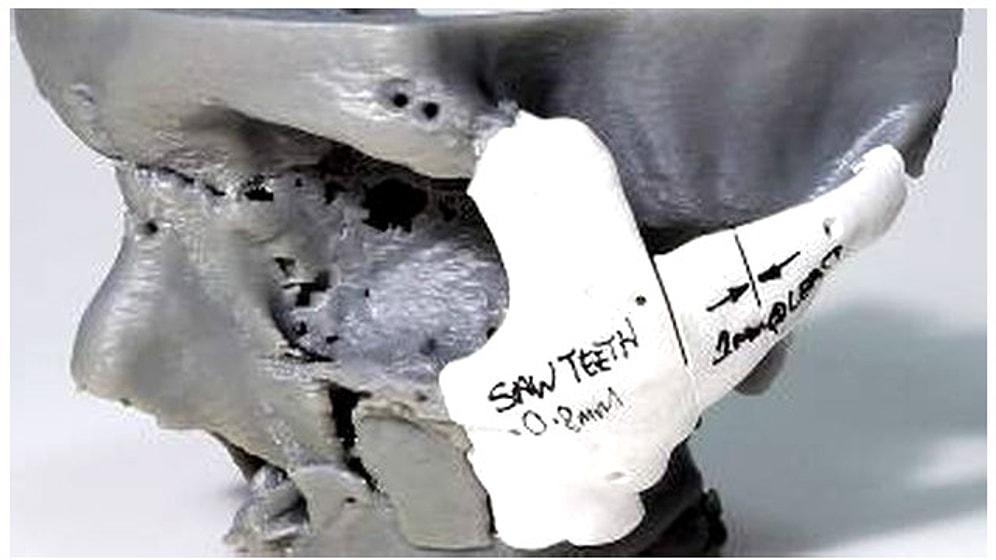

3 Boyutlu Yazıcıyla Yeni Yüz Yapıldı

İngiltere'de motosiklet kazasında yaralanan bir gencin yüzü, 3D teknolojisiyle yani üç boyutlu yazıcı kullanılarak yeniden yapıldı. Stephen Power'ın, tedavisinin her aşamasında üç boyutlu yazıcı kullanılan dünyadaki ilk hasta olduğu düşünülüyor. İngiltere'de Swansea kentinde yapılan ameliyatta, kazadan aylar sonra, özel olarak uyarlanmış ve basılmış modeller, plakalar ve implantlar kullanıldı. Ameliyatı gerçekleştiren Morriston Hastanesi doktorları, Power'ın yeni yüzünü yapmadan önce elmacık kemiklerini yeniden kırdıklarını açıkladılar. Ekip, simetriyi sağlamak için, Power'in kafatasının tomografisini çektiklerini ve üç boyutlu yazıcı ile bastıkları plakaları kullanarak bir modelini oluşturduklarını söyledi. Modelin oluşturulmasından sonra yapılan ameliyat, sekiz saat sürmüş. İngiltere, 3D teknolojisini ameliyatlarda kullanan öncü ülkelerden biri. Daha önce üç boyutlu yazıcı ile doğuştan gelen sorunlar onarılıyordu. Power, 2012'de geçirdiği kazada, kask taktığı halde birden çok darbe ile yaralanmış ve dört ay boyunca hastanede kalmıştı. 29 yaşındaki Power, geçirdiği kazayı şöyle anlatıyor: 'Kazayı hatırlamıyorum. Tek hatırladığım kazadan 5 dakika öncesi ve birkaç ay sonra hastanede kendime gelişim. Her iki elmacık kemiğimle birlikte, üst çenemi ve burnumu kırmışım. Aynı zamanda kafatasımı çatlatmışım.' Çene ve yüz cerrahı Adrian Sugar, 3D teknolojisi sayesinde estetik ameliyatlarda artık tahmin yürütmeye gerek kalmadığını söylüyor ve sözlerine şöyle devam ediyor: 'Elde ettiğimiz sonuçlar öncekilerle karşılaştırılacak gibi değil, bugün elde ettiğimiz sonuçlar, daha önce elde ettiklerimizden çok daha ileride.' Sugar, bu yöntemle daha az hata yaptıklarını da vurguluyor: 'Artık herkes tahmin yürüterek ameliyat etmenin yeterince iyi olmadığını düşünüyor.' Daha önce Belçika'da basılan ve tıbbi kullanıma uygun titanyum implantlar kullanılarak kemiklerin yeni şeklini koruması sağlanıyordu. Power, geçirdiği ameliyatın sonuçlarına baktığında, yüzünün kaza önceki haline ne kadar benzediğini gördüğünü ve kendisini dönüşmüş hissettiğini söylüyor. 'Bu ameliyat hayatımı değiştirdi' diyen Power, sözlerine şöyle devam ediyor: 'Ameliyatın ertesi günü uyandığımda, yarattığı farkı hemen hissettim.' Ameliyat öncesinde maske kullanan Power, artık özgüvenin arttığını söylüyor: 'Artık kendimi gizlememe gerek kalmayacak. Günlük aktivitelere katılabileceğim, insanlarla buluşabileceğim, sokaklarda yürüyebileceğim ve hatta kamuya açık yerlere gidebileceğim.' Ameliyat, Swansea cerrah ekibi ve Cardiff Metropol Üniversitesi'ndeki bilim insanlarıyla işbirliği yapan 'Ameliyatta Estetik Teknolojileri Merkezi'nin (Cartis) projesiydi. Tasarım mühendisi Sean Peel, bu deneyimin İngiliz Sağlık Hizmetleri'ni üç boyutlu yazıcı kullanmaları konusunda teşvik etmesi gerektiğini söyledi. Peel 'Bu teknoloji oldukça karmaşık bireysel vakalarda, karmaşık ama uzun soluklu bir tasarım süreci olarak kullanılabiliyor. Bir sonraki zaferimiz, bu yöntemin daha yaygın kullanılması. Böylece hem daha ucuza mal edilir hem de tasarım teknikleri gelişir' dedi. Power'ın geçirdiği ameliyat şu anda Londra'daki Bilim Müzesi'nde 'Üçboyutlu Basım: Gelecek' ismiyle sergileniyor.BBC